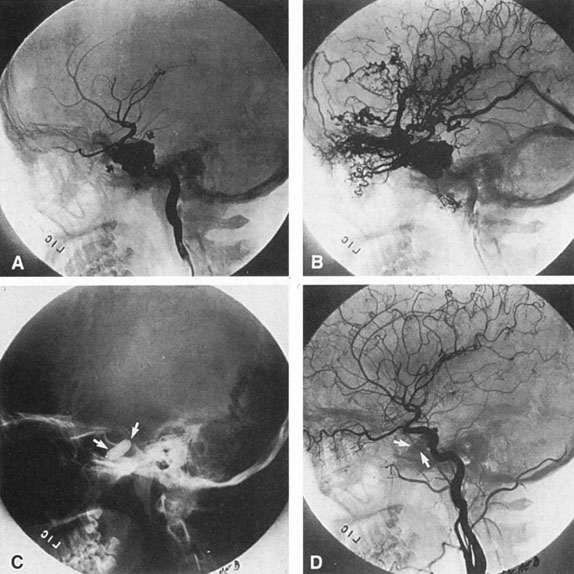

The detection of intracranial AVMs is facilitated by CT scanning and MRI (Fig. 10),88 but optimal management requires selective angiography89 that assesses the size and configuration of the mass, the number and location of feeding arteries, the flow characteristics and degree of steal from brain parenchyma, and the pattern of venous drainage.

Fig. 10. Neuroimaging of arteriovenous malformation. A: Coronal magnetic resonance imaging (MRI) (TR, 600 ms; TE, 20 ms) shows wedge-shaped vascular mass extending from the surface of the parietal cortex (white arrows) to the lateral ventricle (black arrows; asterisk, arterial feeder). B: Posteroanterior left arteriogram of the same lesion. C: Axial computed tomography scan with contrast enhancement. D: Axial MRI of a large arteriovenous malformation, first echo (TR, 2000 ms; TE, 20 ms). E: Second echo (TR, 2000 ms; TE, 90 ms). (From Smith HJ, Strother CM, Kikuchi Y, et al: MR imaging in the management of supratentorial intracranial AVMS. AJNR Am J Neuroradiol 9:225, 1988.)